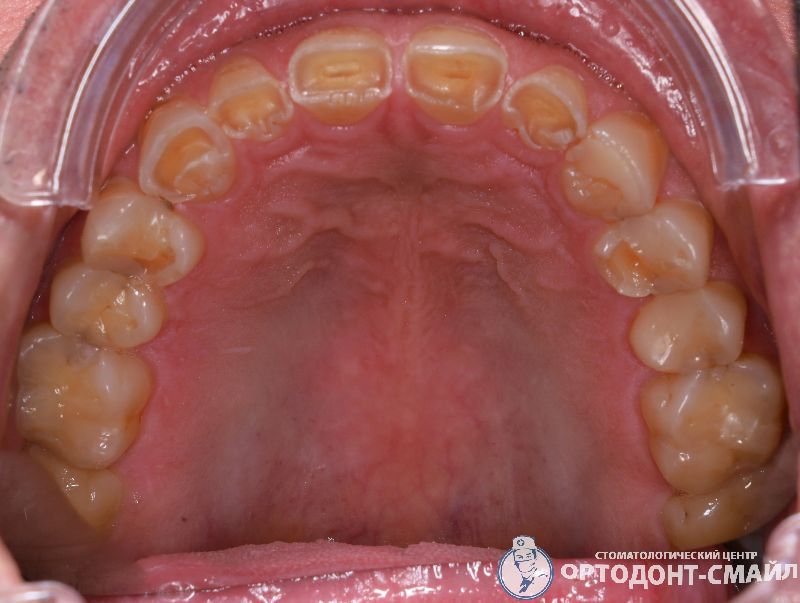

Диагноз: прямой травматический прикус, повышенная стираемость зубов.

Проведено: лечение ВНЧС, тотальная реабилитация по поднятию прикуса диоксидом циркона

верхняя челюсть